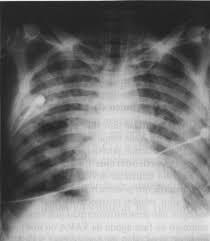

Raio x na SDRA

Infiltrado misto que pode poupar algumas regiões do pulmão

Se acomete os 2 lados = síndrome do pulmão branco

Infiltrado misto = componente alveolar e intersticial bilateral